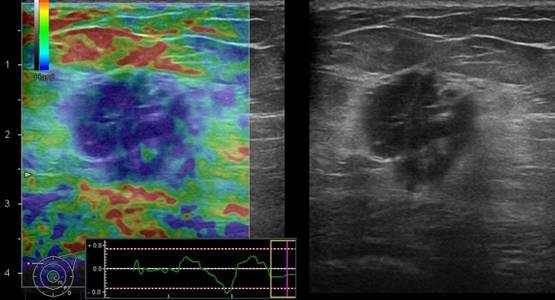

Ung thư vú

» Thông tin: Nữ giới – 51 tuổi.

» Lâm sàng: Khối tuyến vú.